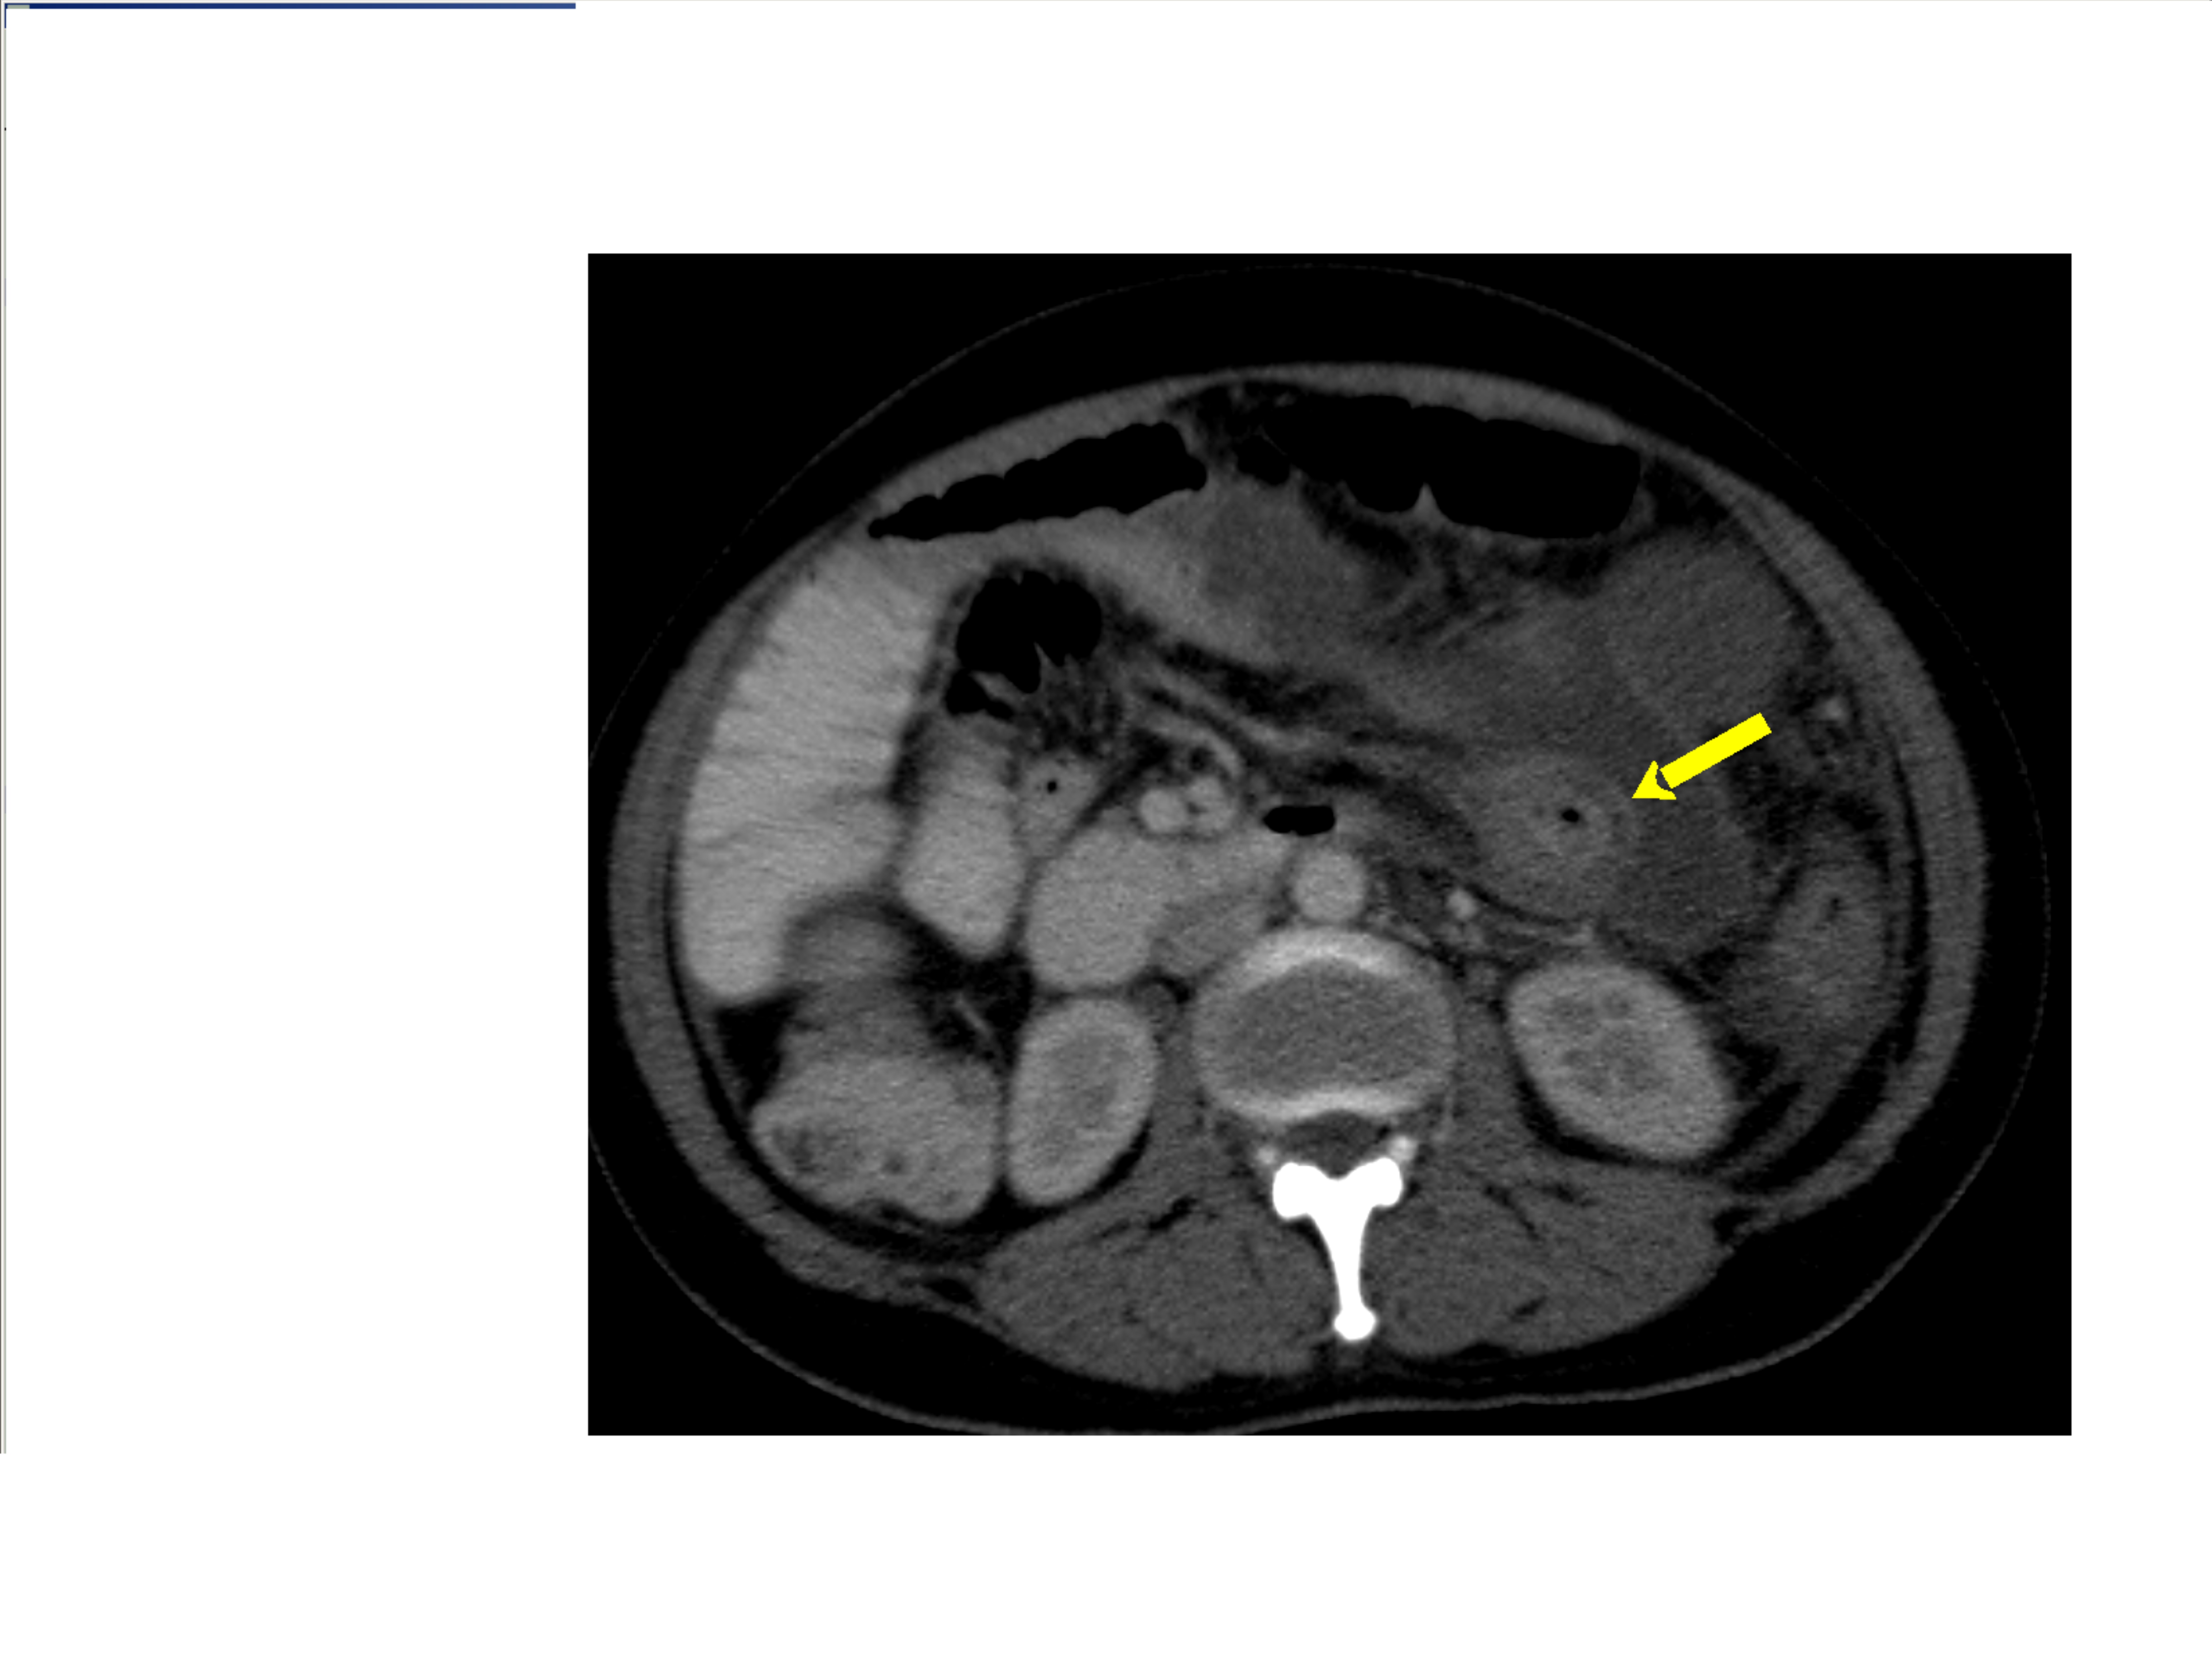

Small bowel obstruction is a common clinical presentation that presents a diagnostic conundrum. Over the last 2 decades, there has been a paradigm shift in the radiological investigation of small bowel obstruction (SBO) and in the indication for and timing of surgical intervention. Cross sectional imaging (predominantly computed tomography) has largely replaced the widespread use of radiographic small bowel follow-through studies as the imaging modality of choice for SBO. This article illustrates the current imaging modalities available for diagnosis of small bowel obstruction. (Full text available online at www.medpharm.tandfonline.com/ojfp) S Afr Fam Pract 2015; DOI: /10.1080/20786190.2014.977052